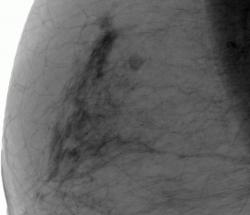

СЛУЧАЙ РЫБАКОВОЙ Л. А. "Инфильтрирующий рак правой молочной железы".

"Инфильтрирующий рак правой молочной железы".